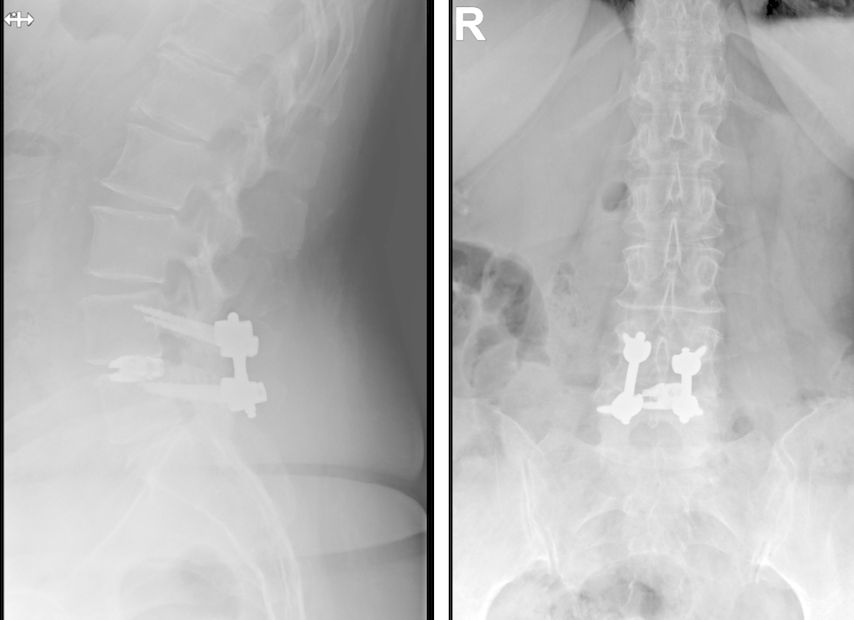

Beispiel für die Implantation zervikaler Pedikelschrauben. In diesem Fall kam es bei einem 61-jährigen Patienten 10 Jahre nach anteriorer zervikaler Diskektomie und Fusion (ACDF) C4/5 und ventraler Verplattung C4–6 zu einer Ankylosierung auch von C6/7. Nach Sturz kam es zu einer Fraktur bei C6/7 mit begleitender Bogenfraktur und auch Beteiligung der dorsalen Ligamenta (Abb. 1 und 2). Klinisch bestanden ausgeprägte Nackenschmerzen und kein neurologisches Defizit. Es wurde die Indikation der dorsalen Verschraubung von C4 auf Th1 gestellt. Intraoperativ wurde routinemäßig zusätzlich eine kleine Referenzschraube in einer Lamina – entfernt von der Dornfortsatz-Referenzklemme für die Navigation – gesetzt. Mit dieser konnte intraoperativ die Genauigkeit der Navigation exakt überprüft werden (Abb. 4 und 5). Mittels navigierter High-Speed-Fräse wurden die Schraubenkanäle vorgebohrt (Abb. 6), im Anschluss wurde der Bohrkanal ausgetastet und die Schrauben wurden implantiert. Abbildung 7 zeigt eine Röntgenkontrolle 3 Monate postoperativ.

Abb. 4: Screenshot der Navigationssoftware intraoperativ (Stealth Station S7). Es erfolgt die intraoperative Verifizierung der Navigationsgenauigkeit mittels kleiner Schraube in der Lamina, positioniert idealerweise entfernt von der Dornfortsatz-Referenzklemme. Die navigierte Fräse wird im Situs exakt auf die Schraubenmitte gerichtet, und die Navigation bestätigt die Genauigkeit | |